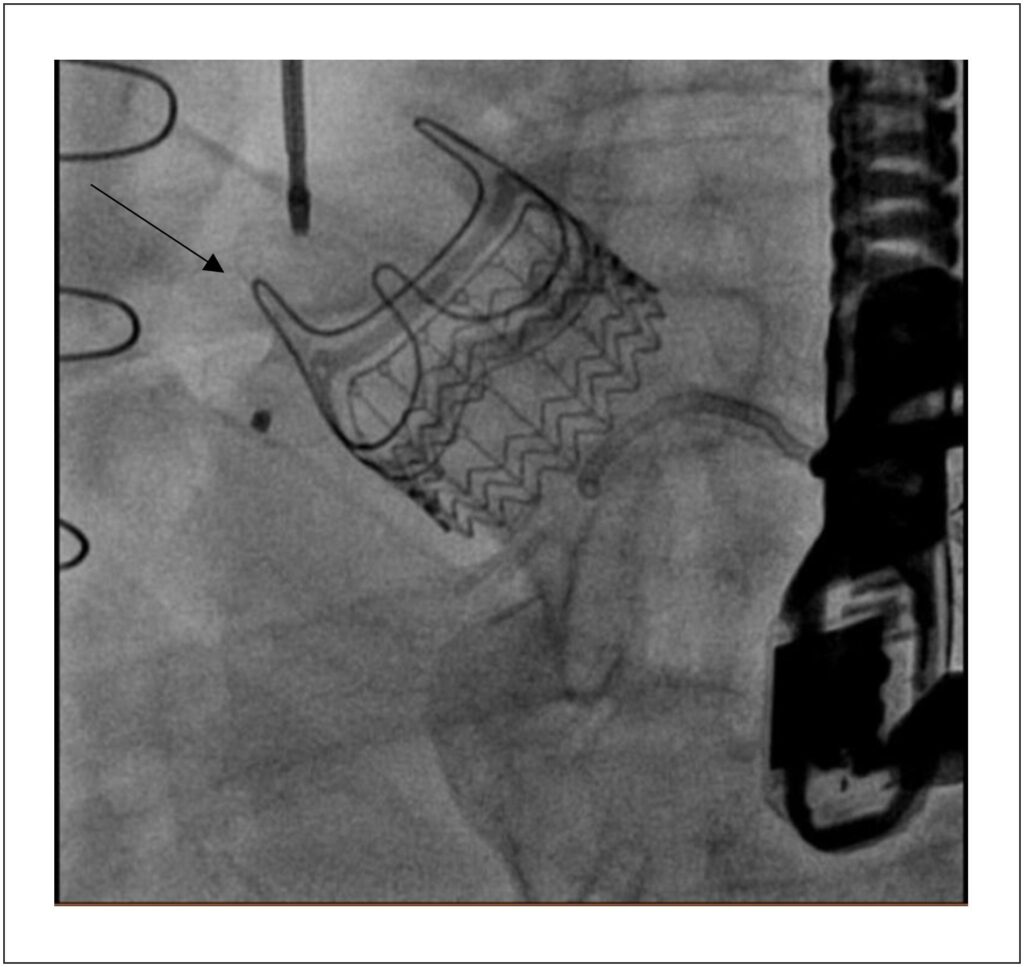

We describe the first case in the literature of transcatheter correction of aortic-right ventricular (Ao-RV) shunt after aortic valve replacement (AVR) with an Intuity® prosthesis (Edwards Lifesciences). A 79-year-old patient with a history of coronary artery bypass grafting and aortic regurgitation underwent AVR using a rapid-release 25-mm Intuity® prosthesis. After 45 days, he presented with severe heart failure, and an Ao-RV shunt was identified on transthoracic echocardiography. Given his history of previous cardiac surgeries, percutaneous correction was attempted. Initially, an attempt was made to catheterize the defect via the transapical approach, which was unsuccessful. The right femoral artery was punctured, and the shunt was catheterized via the aorta, with the implantation of a MemoPart ventricular septal defects (VSD) occluder, resulting in a significant reduction of the shunt. The patient was then transferred to the intensive care unit. However, there was no satisfactory clinical improvement, and transthoracic echocardiography revealed persistent Ao-RV shunt. Therefore, the surgical team opted for a new approach through the femoral artery and a second MemoPart VSD occluder was implanted. A transesophageal echocardiogram showed no leak, and the patient progressed satisfactorily and was discharged from the hospital. Shunts after AVR are rare. In these conditions, percutaneous management is a safe and feasible technical option. This is the first case reported in the literature of this type of complication after Intuity prosthesis implantation.